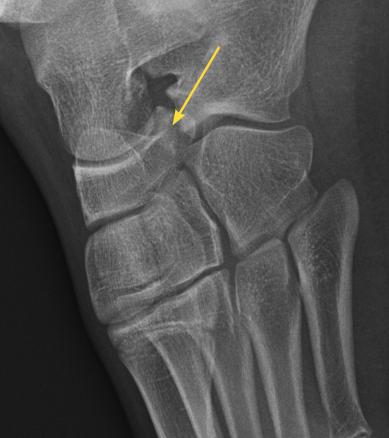

Le bec calcanéen long correspond à une coalition calcanéonaviculaire incomplète. Ici il s'agit d'un bec calcanéen long chez un garçon de 14 ans avec un aspect irrégulier et une diminution de l’espace entre calcanéus et naviculaire.